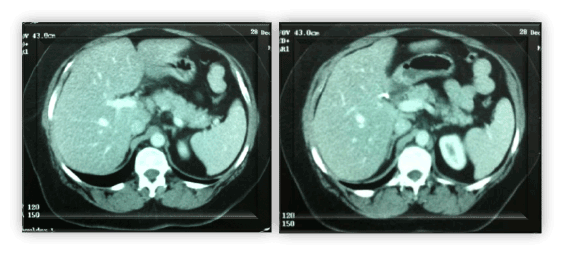

腹部CT (Computed tomography, CT)如图1所示,显示小的多发低密度区域,主要位于门脉周围区域。胸部CT示弥漫性微结节混浊。

弓形虫病特异性血清学阳性,患者接受阿苯达唑400 mg / d治疗,持续15天。嗜酸性粒细胞率为1600 /mm3.治疗1个月,6个月后腹部CT示肝结节完全消失(图2)。

图1所示。腹部计算机断层扫描显示弥漫性肝低密度病变。

图2。随访计算机断层扫描显示治疗六个月后肝脏病变消失。